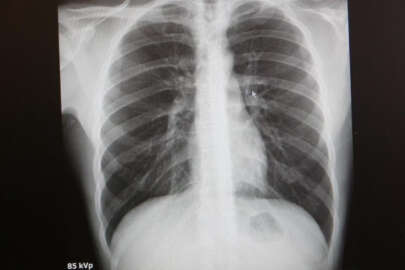

Uzmanlar, deprem bölgelerinde bulunan vatandaşların asbest ve benzeri maddelere maruz kalmamaları gerektiği konusunda uyarılarda bulunuyor. Marmara Üniversitesi Pendik Eğitim Araştırma Hastanesi Göğüs Hastalıkları Anabilim Dalı Başkanı Prof. Dr. Sait Karakurt, deprem bölgelerinde yıkım esnasında ortaya çıkan asbest ve benzeri maddeler hakkında bilgiler aktardı. Prof. Dr. Karakurt, ayrıca yaklaşan Ramazan ayı öncesinde KOAH hastalarına da tavsiyelerde bulundu.

“Akciğere saplanıp, yok edilemedikleri için zaman içinde kanserleşmeye neden olurlar”

Prof. Dr. Sait Karakurt, “Yaşadığımız felaketlerden dolayı insanlar birçok zarar verici madde ile karşı karşıya kalıyorlar. O ortamlarda enfeksiyon sıklığı artıyor. Yangın sırasında bir takım zararlı maddeler oluşuyor. Bunlar sağlığı bozuyor. Bozulan en önemli organlardan biri de akciğerlerimiz. Yıkım sırasında asbest gibi, silisyum gibi maddeler akciğere dokunan en önemli parçacıklardan. Bunların etkisiyle akciğerlerde birkaç hafta içerisinde nefes darlığı ve öksürük ile giden ciddi sıkıntılar meydana gelebilir. Özellikle silisyum ve asbeste maruz kalmada 10 yıldan sonra bir takım problemler olabilir. Asbeste bağlı akciğerde plaklar oluşabilir, sıvı oluşabilir. Akciğer zarından kaynaklanan kanserler de asbestli hastalarda zaman içinde gözükebilir. Bu kişilerin takip edilmesi gerekebilir. Yıkım sırasında oluşan parçacıkların, 10 mikrondan küçük olanların akciğere girme ihtimali vardır. Asbest liflerini bir dikiş iğnesine benzetebiliriz. İnce uzun liflerdir. Bunlar akciğere saplanıp, yok edilemedikleri için sürekli iltihap reaksiyonu oluşturup zaman içinde kanserleşmeye neden olurlar” dedi.